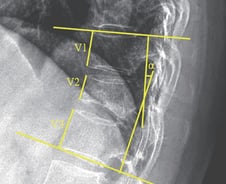

우리 몸에는 뇌에서부터 등 아래까지 신경 다발이 지나가는 척수가 있다. 척수가 지나가는 경추(목뼈)가 좁아지거나 눌리면 신경이 압박받아 손과 발, 몸 전체에 이상이 나타나는데 이는 흔히 '목 중풍'이라 부르는 '경추 척수증'의 주된 증상이다. 경추 척수증은 보통 손발과 팔다리 양쪽에 증상이 나타나고 서서히 진행되는 양상을 보인다. 젓가락질과 단추 채우기, 글쓰기 같은 손놀림이 둔해지며 양쪽 팔다리 힘이 약해진다. 손이나 발이 저리고 감각이 둔해지고, 휘청거리거나 발이 자주 걸리는 증상이 나타난다. 경추 척수증은 나이가 들면서 디스크나 뼈가 자라나 척수를 눌러 생길 수 있다. 또 사고 등 목이 충격을 받거나 후종인대가 딱딱하게 굳는 병(후종인대 골화증)으로 신경이 눌리기도 한다. 특히, 경추 척수증과 뇌 질환은 모두 신경계 기능 장애를 유발한다는 점에서 뇌졸중, 파킨슨병, 알츠하이머를 포함한 뇌 질환과 혼동하기 쉽다. 모두 △보행 장애 △감각 둔화 △사지 힘 빠짐 △요실금 또는 배뇨 지연 등의 증상이 나타나는 공통점이 있다.

평소 구부정한 자세로 컴퓨터 앞에서 업무를 보고, 스마트폰 삼매경에 빠진 현대인은 '목 통증'을 달고 사는 경우가 많다. 거북목 증후군이나 근막동통 증후군, 목 디스크처럼 과거에는 다소 생소했던 근골격계 질환도 어느새 현대인의 '고질병'으로 자리매김하는 모습이다. 이유는 있다. 전자기기에 몰입하다 보면 자신도 모르게 어깨를 움츠리고 목을 앞으로 쭉 빼는 자세를 취하게 된다. 무게 중심이 앞으로 쏠리면서 목뼈를 지탱하는 목 뒷부분의 근육과 인대가 과도한 힘을 받아 팽팽하게 당겨져 비정상적으로 늘어난다. 이동찬 힘찬병원 척추클리닉 원장(신경외과 전문의)은 "정상적인 C자형 경추(목뼈) 만곡이 '일자형'이나 '역 C자'형으로 바뀌면서 목덜미에서 어깨까지 통증과 뻐근함이 느껴진다"며 "근육이 과도하게 긴장해 두통이 발생하기도 한다"고 설명했다. 거북목 자세는 머리가 제 위치에 있을 때보다 목에 4~5배 이상의 하중을 가하는 것으로 알려져 있다. 이런 자세를 장기간 유지하면 목과 어깨의 통증을 부르고 방치할 경우 만성 통증을 부르거나 목 디스크로 이어진다.